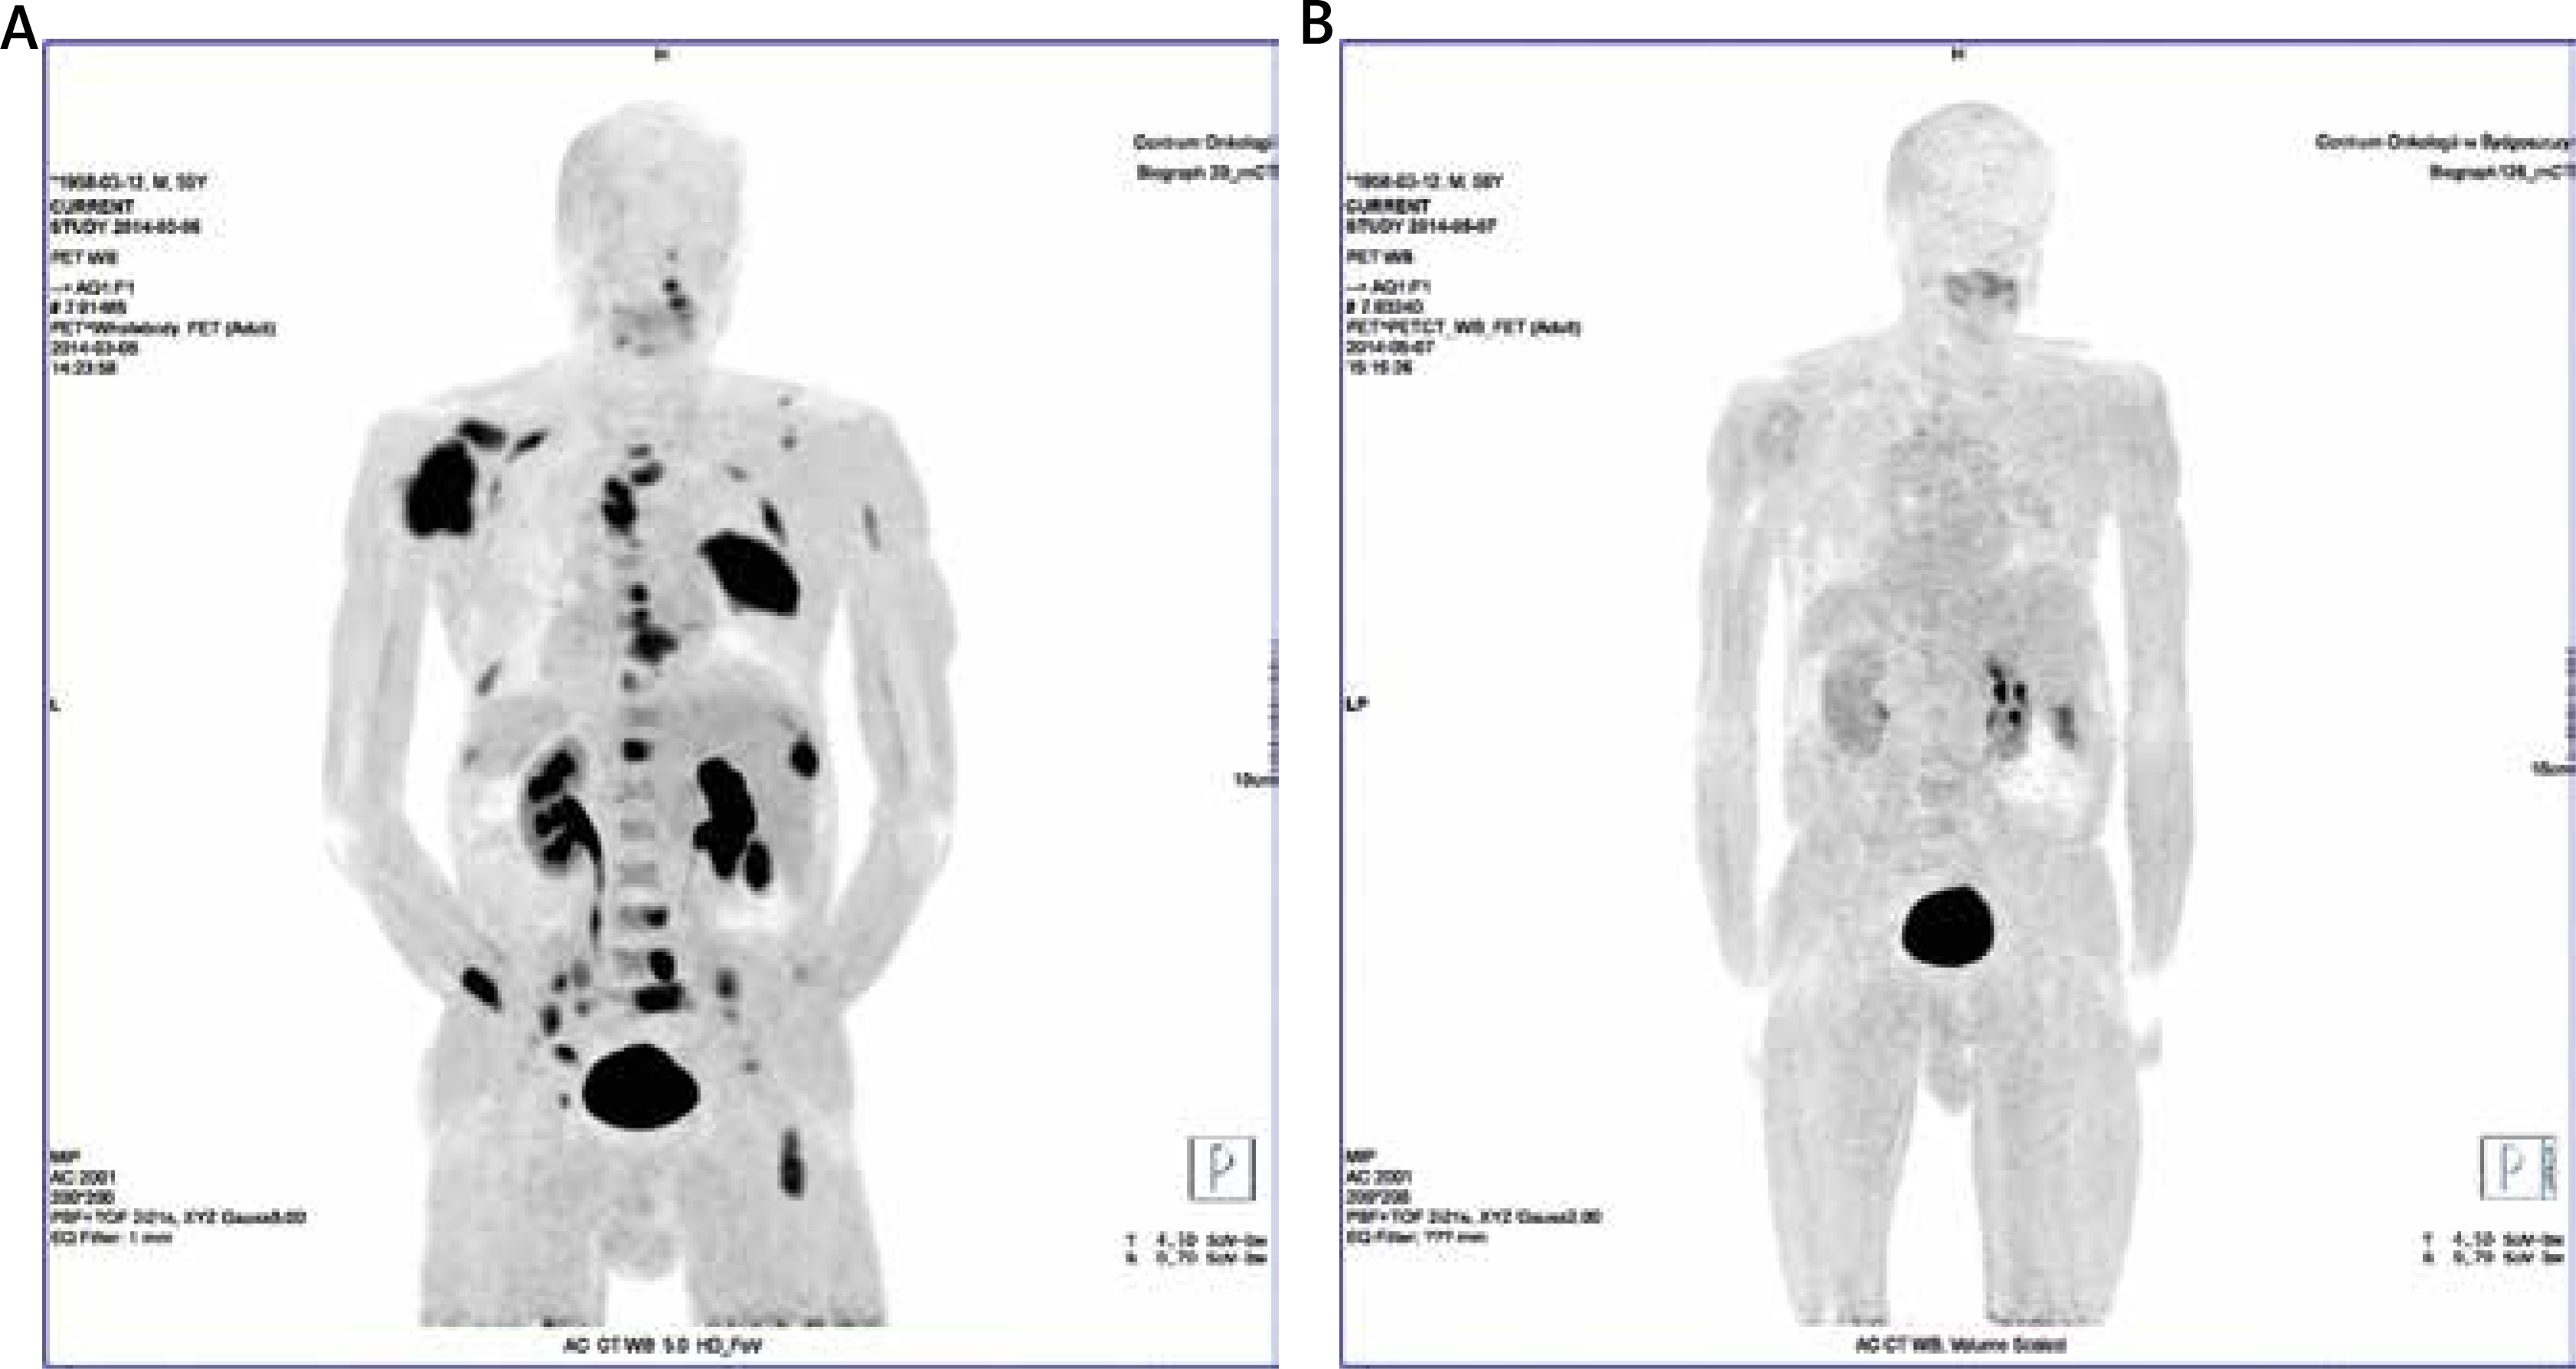

Fig. 2

The same patient after completion of therapy. A) Computed tomography (CT) – lytic lesions localised in the sternum – no difference to the status before therapy. B) 18F-FET PET/CT, fusion image with low FET uptake in the lytic lesion visible on CT in sternum. C) Computed tomography – lytic lesion localised in the right iliac crest – no difference to the status before therapy. D) 18F-FET PET/CT fusion image with low FET uptake in iliac crest